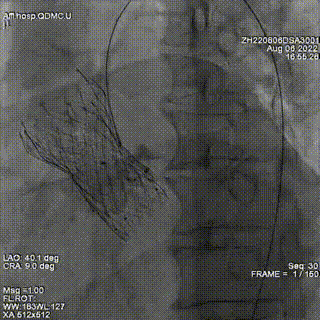

通过交换导丝置换鞘管,置入入第一枚封堵器6mm ADOII。

确定第一枚封堵器置入位置理想,但造影仍提示瓣周反流。

根据造影确定瓣周漏位置,在第一个封堵器旁探查,再次通过瓣周漏,置换鞘管后置入第2枚封堵器,仍选择6mmADOII。封堵器释放后位置良好。